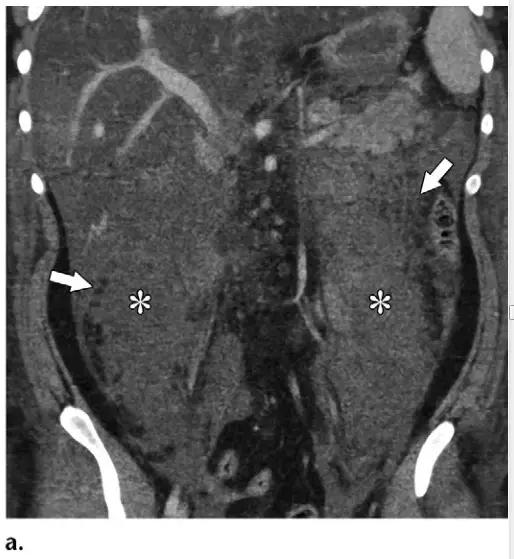

同时受累的亚型:表现为胰腺及胰周无强化坏死物,多累及小网膜囊和肾前间隙(图 3a)。

胰周型:表现为胰腺强化正常,而胰周坏死,坏死物可包括不等量的液体和和非液性成分,约占坏死性胰腺炎的 20%(图 3b)。

胰腺型:仅占 5%,没有胰周坏死物。在发病的前几天胰腺可仅表现为水肿,局限或弥漫性低强化,可能很难与 IEP 相鉴别,在这些病例中,在发病 5~7 天后再次行 CT 增强扫描可以提高诊断坏死性胰腺炎的准确率。

图 3 坏死性胰腺炎亚型在增强轴位 CT 的表现。a 胰腺和胰周同时受累的 58 岁女性患者,胰体无强化(*),正常强化的胰尾(黑箭头),小网膜囊内 ANC(白箭头)。b 仅胰周受累的 18 岁男性患者,可见一周为大片不均质密度(箭头),和 ANC 相符。胰腺实质密度正常(*)。c 仅胰腺实质受累的 33 岁男性患者,可见大片局限无强化的胰腺实质和脂肪密度(*),诊断为 WON。仅周边可见少量残余强化的胰腺实质(箭头)